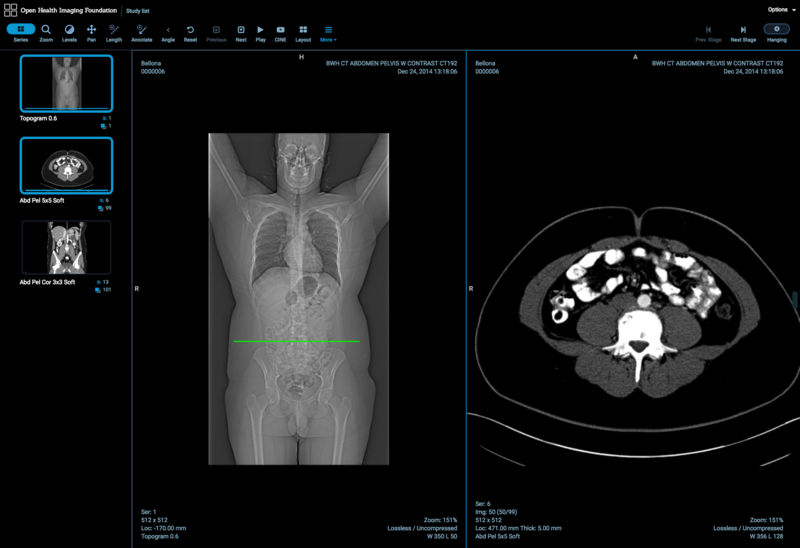

Project Week 25/DICOM Segmentation Support for Cornerstone and OHIF Viewer

Illustrations